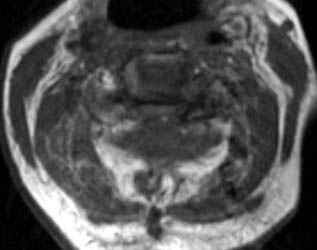

75 y.o. female with about a two-year history of continued gait abnormalities

and decreased dexterity. On examination her strength was normal, however, she

had bilateral Hoffmann signs as well as bilateral Babinski signs. Her strength

was 5/5 but her gait was ataxic. Magnetic resonance imaging showed severe

stenosis at C3, C5 and C6 levels. She underwent C3-C6 laminectomies.

Immediately post-operatively she did well, however, within 36 hours of the

operation, she slipped and fell due to spilled milk on the floor . After that

injury, the patient was neurologically intact. However, on postoperative day #2

for morning rounds, the patient was noted to be confused and weakened on the

left side, both arm and leg, leg more than the arm. An immediate CAT scan of the

brain and cervical spine was obtained. Immediate MRI was also obtained.

Non-enhanced sagittal T1 (A), sagittal T2 (B) and axial T1

images demonstrate a large fluid collection,

predominantly low signal on T1, bright on T2 with a few areas of T1 hyperintesity

mixed within. These constellation of findings are consistent with a

post-operative epidural hematoma with blood products of various ages. There is

severe severe spinal canal stenosis at C3-4, and very severe spinal canal

stenosis at C4-5 and C5-6. The cord is markedly flattened in the

anterior-posterior dimension, to approximately 2-3 mm secondary to mass effect

from this fluid collection. There is abnormal T2 weighted hyperintensity within

the substance of the cord at the C5-6 and C6-7 levels, consistent with some

edema.